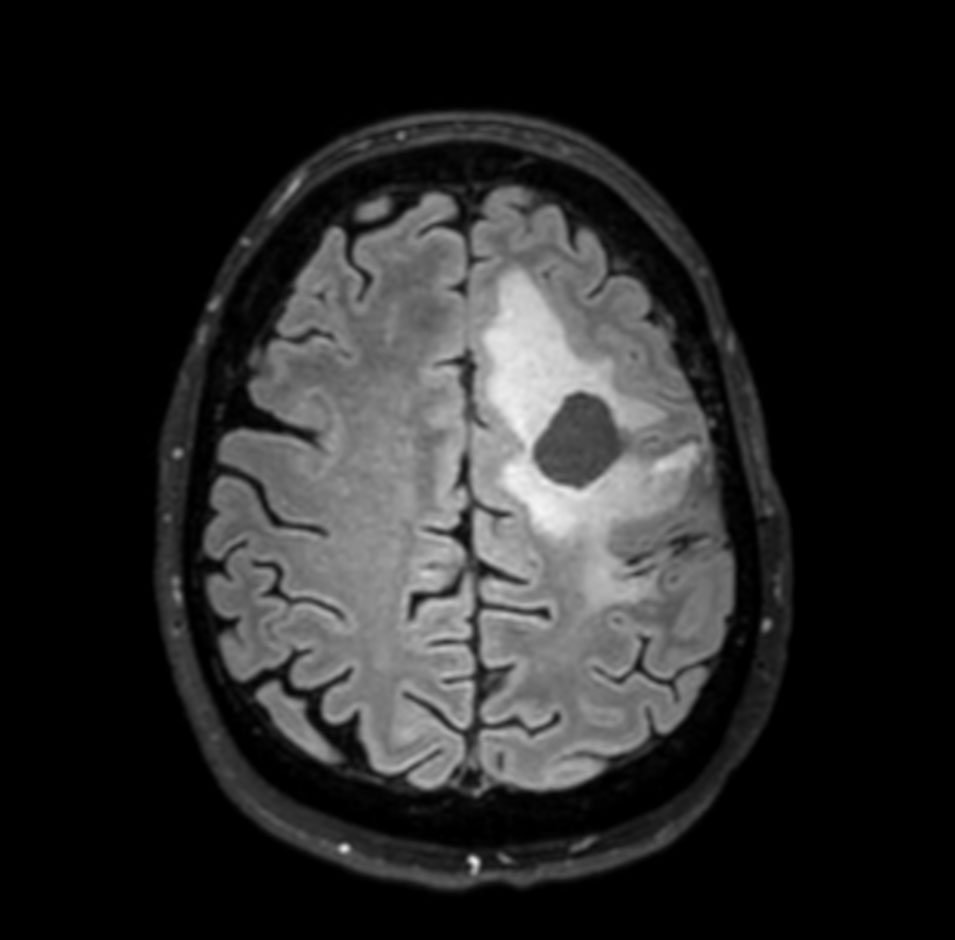

Axial T2w TSE